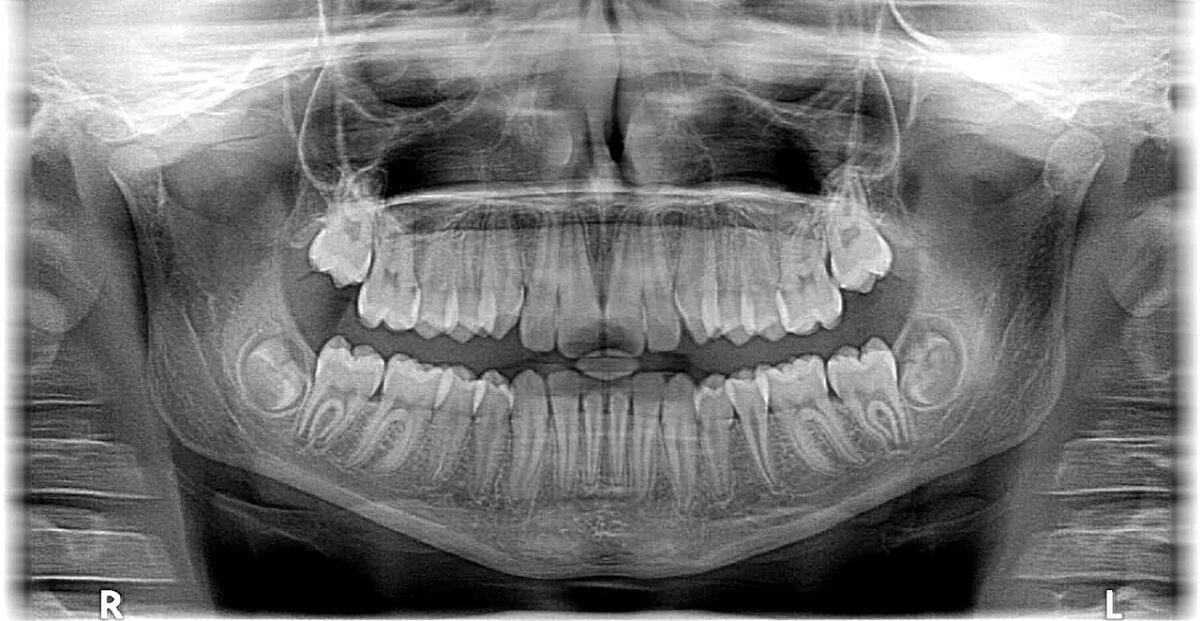

Какую помощь врачу могут оказать методы рентгеновских исследований? Рентген позволяет проводить неинвазивные исследования состояния внутренних органов, обнаружить на ранних стадиях всевозможные опухоли, поражения легких, уточняет положение костей при переломах и вывихах.

• Существует рентгенография — изображение фиксируется на специальной пленке прямым попаданием рентгеновских лучей.